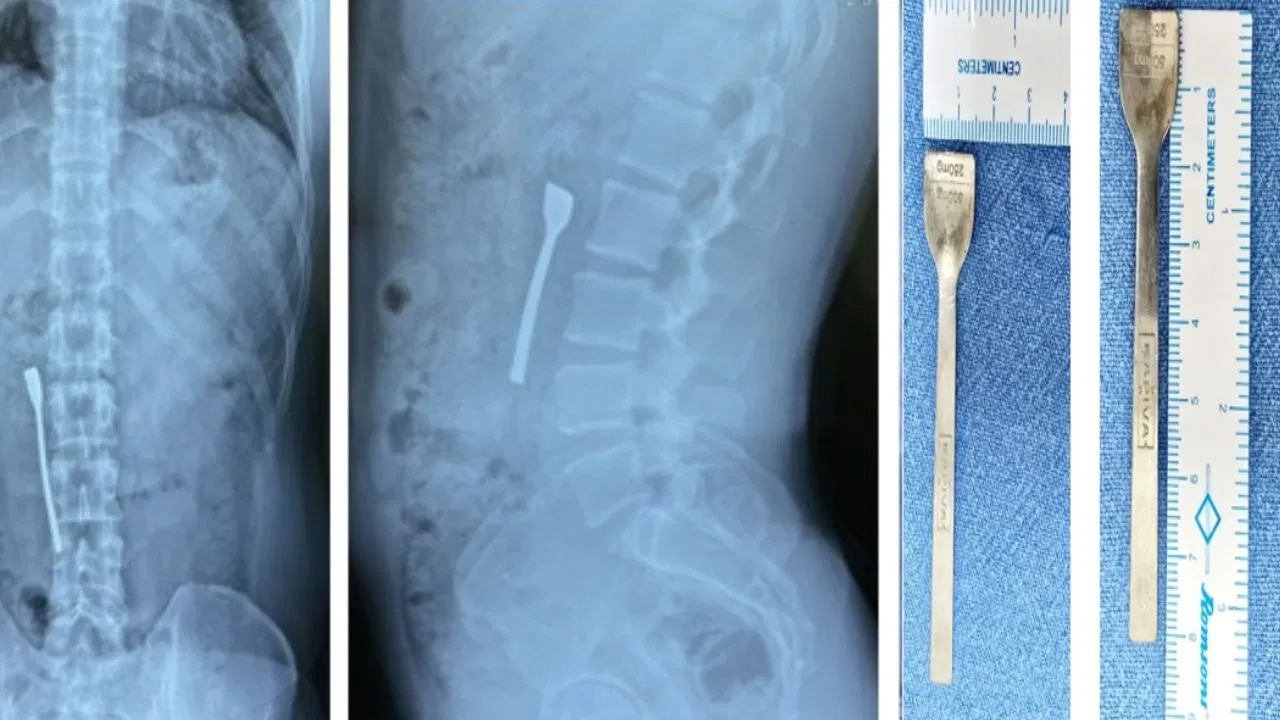

दिल्ली का एक 30 साल का युवक गलती से 8 सेंटीमीटर लंबी चम्मच निगल गया. यह चम्मच उसकी ऊपरी आंत में फंस गई थी. युवक को तुरंत उत्तरी दिल्ली के एक मल्टी सुपर-स्पेशलिटी हॉस्पिटल में ले जाया गया, जहां से शुरुआती जांच के बाद उसे शालीमार बाग के फोर्टिस अस्पताल की इमरजेंसी में रेफर कर दिया गया था. युवक जब अस्पताल पहुंचा तो उसकी हालत स्थिर दिखाई दे रही थी. हालांकि, एक्स-रे जांच के बाद उसके पेट में चम्मच की पुष्टि हुई.

शालीमार बाग के फोर्टिस अस्पताल में उनके पेट के एक्स-रे सहित कई तत्काल डायग्नोस्टिक इमेजिंग की गई, जिससे पता चला कि उनकी आंत के ऊपरी हिस्से में एक धातु (चम्मच) फंसा हुआ था. मरीज की एनेस्थीसिया में तत्काल इमरजेंसी अपर गैस्ट्रोइंटेस्टिनल एंडोस्कोपी की गई. सर्जिकल टीम ने फोरसेप की मदद से सावधानीपूर्वक मरीज के पेट से चम्मच निकाला. इस सर्जरी के बाद उन्हें 24 घंटे तक निगरानी में रखा गया.